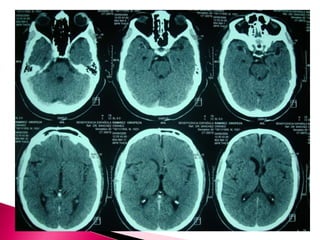

 ¿ La lesion cerebral es causada por una EVC

de tipo isquemico o hemorragico o por una

entidad no vascular?

 Respuesta: clinica y Tomografia

computarizada de craneo simple o RM craneal

simple

 Signo dela arteria cerebral media hiperdensa

 Atenuacion del nucleo lenticular

 Hipodensidad cortical o subcortical

 Edema cerebral

 Borrado de la region insular

 Borrado de surcos corticales

 Compresion ventricular

 Atenuacion de contraste cortico-medular